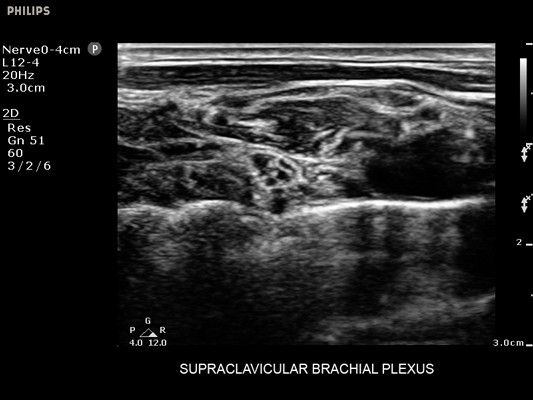

• Диагностика нервов

• Линейный УЗИ датчик Philips L12-4